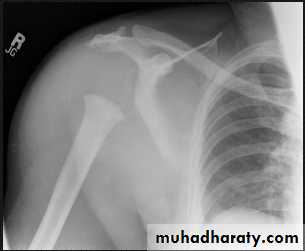

• * Arthritis of proximal joints (hip > shoulder) in 50% ,erosions and osteophytes

• Primary loss of sensation in a joint leads to arthropathy. Distribution helps determine etiology.• Causes

• Diabetes neuropathy: usually foot

• Tertiary syphilis : usually knee

• Syringomyelia: usually shoulder

• Radiographic features

• Common to all types

• *Joint instability: subluxation or dislocation